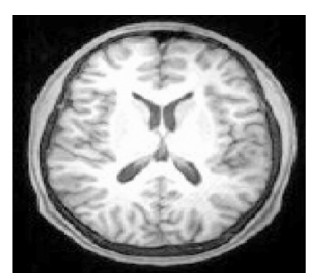

在验证实验中,选择了对比度较低、边缘异常不规则的图像(图 7),传统C-V模型的需要更多迭代次数,导致分割时间增加,而尖锐的边缘使其分割有效面积更小。改进的C-V模型则在一定程度上弥补了传统C-V模型算法分割的不足,如图 8所示。

|

图 7 脑室PET图像 |